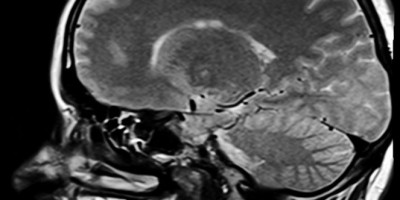

Žena je stigla u bolnicu u severozapadnom gradu Pešavaru nakon što je kleštima pokušala da sama izvuče ekser iz glave, objasnio je doktor Hajder Kan.

Rendgen je pokazao da je ekser od pet centimetara probio vrh ženinog čela, ali nije pogodio njen mozak. Dr Khan je dodao da je korišćen čekić ili drugi težak predmet da se udari.